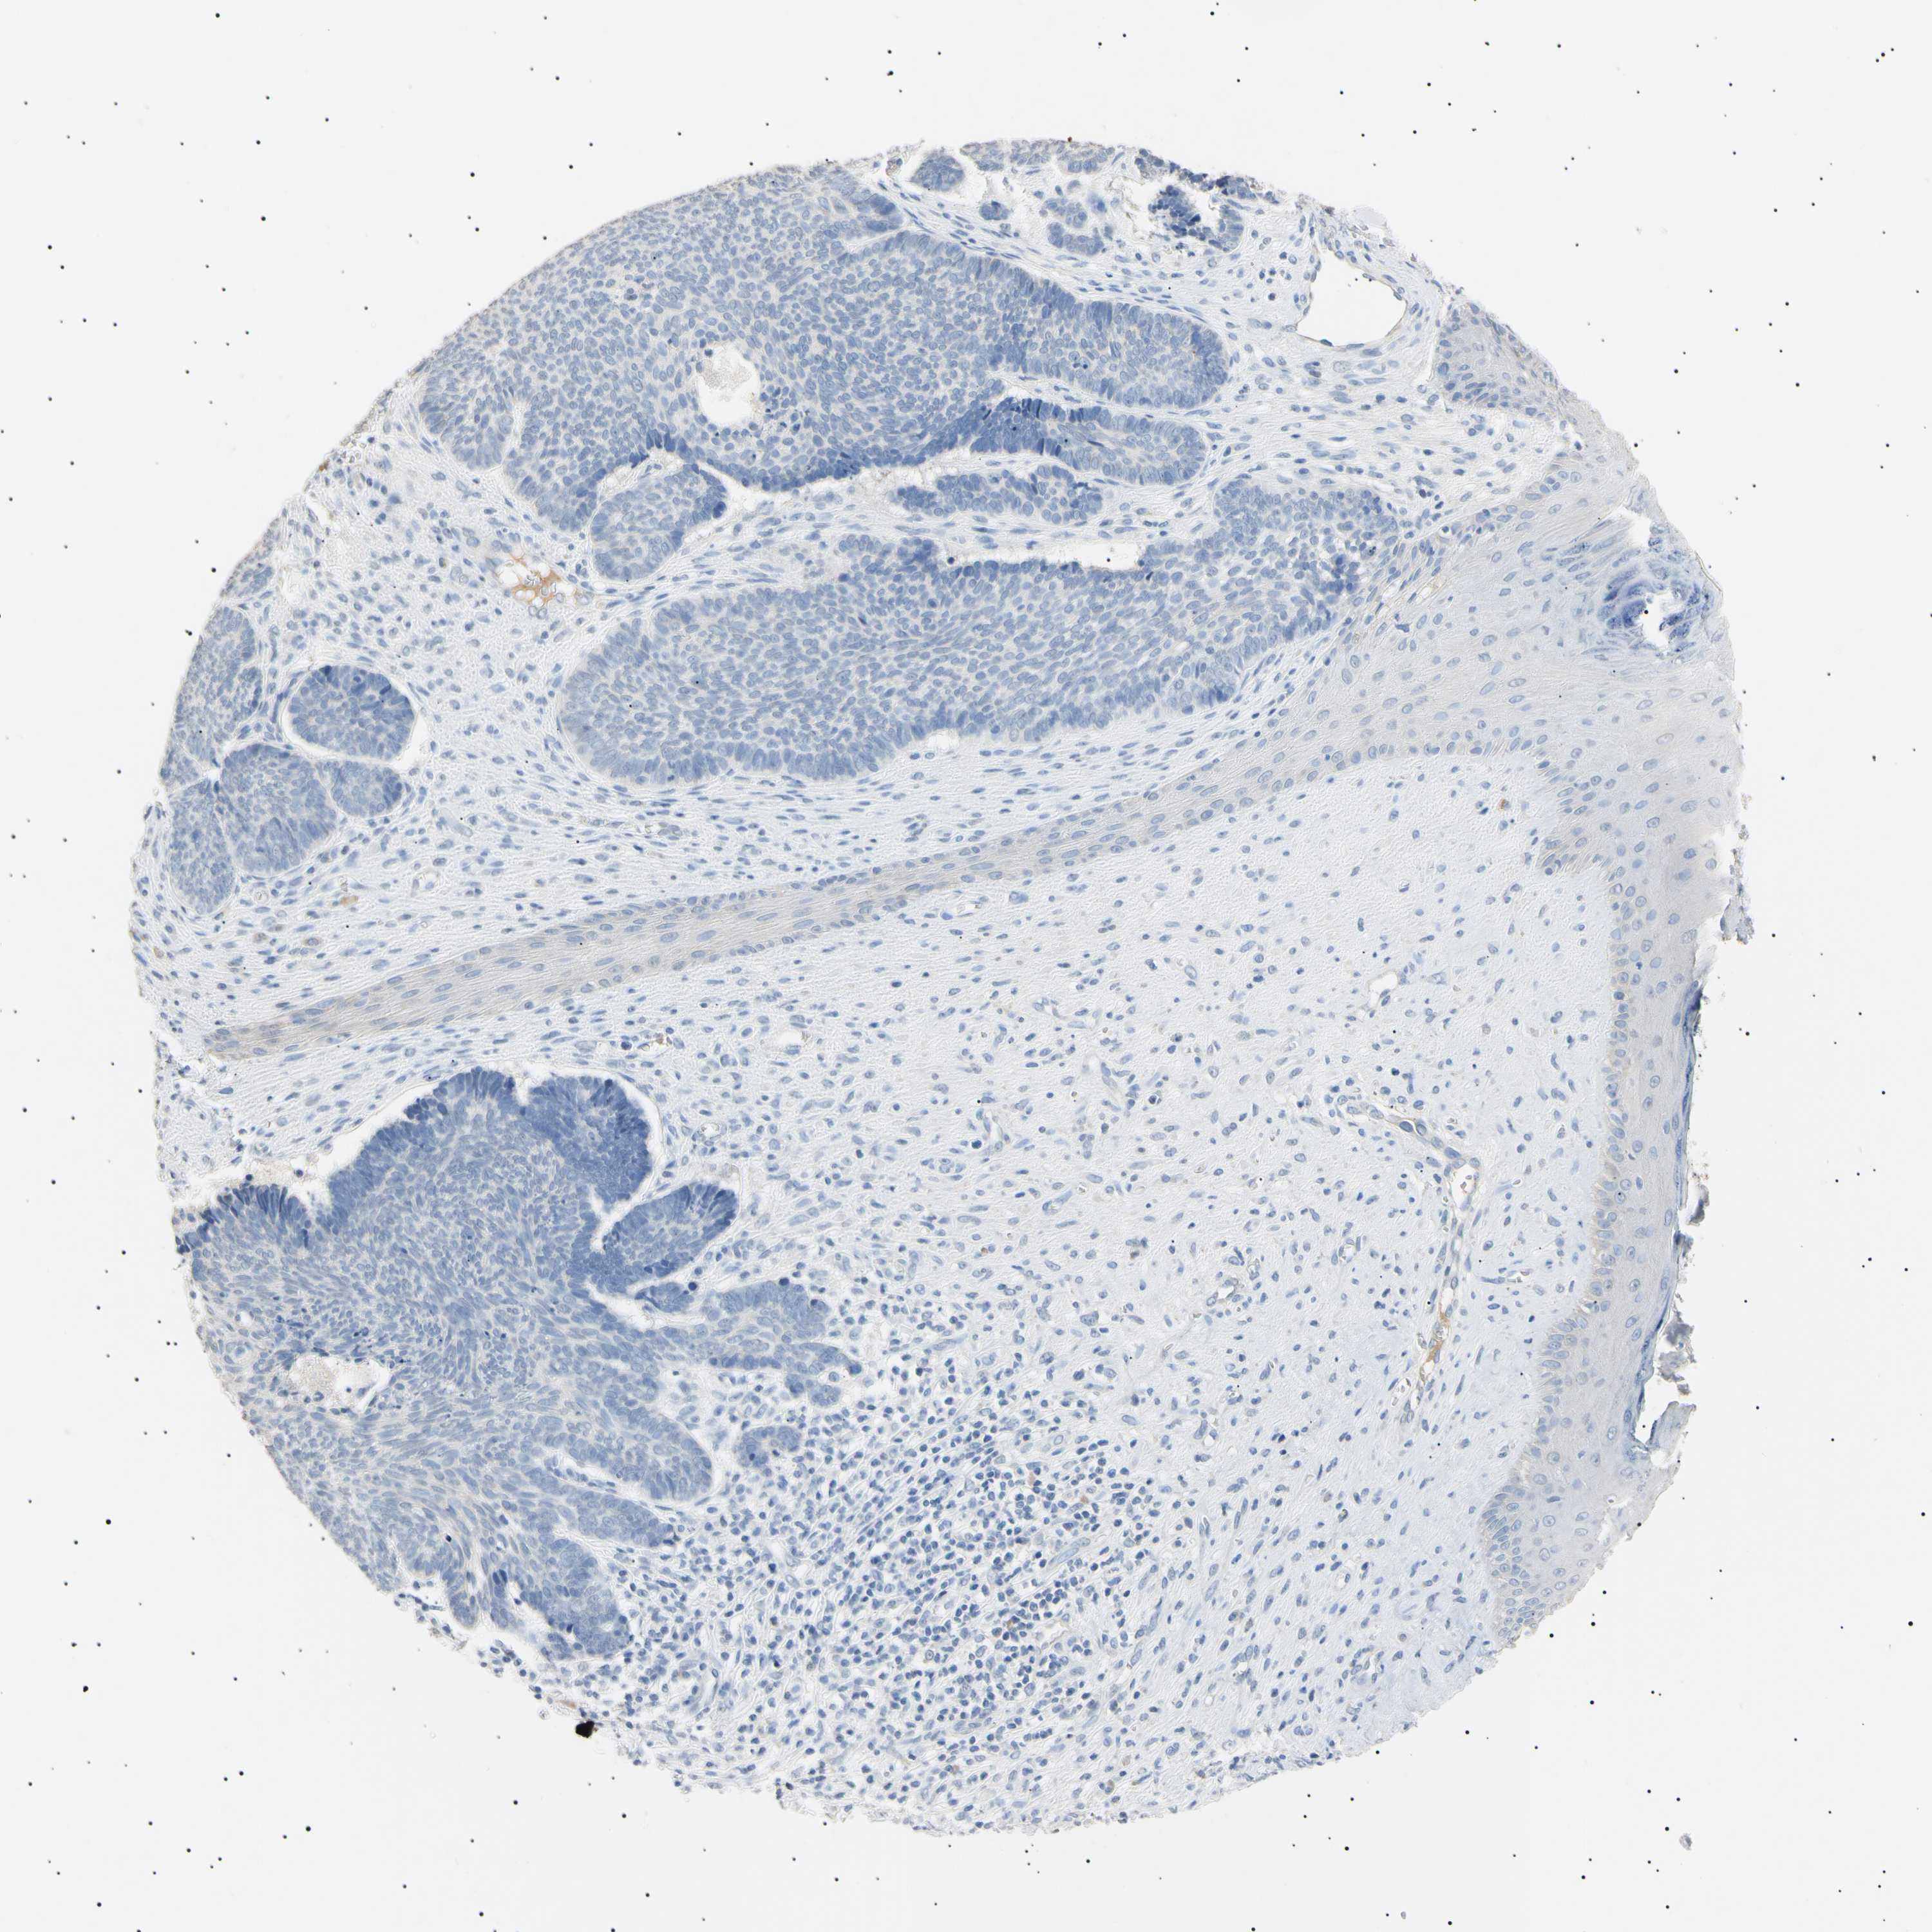

CANCER SKIN CANCER Show tissue menu

Basal cell and squamous cell cancer

SKIN CANCER - Protein expressioni

A mouse-over function shows sample information and annotation data. Click on an image to view it in a full screen mode. Samples can be filtered based on level of antibody staining by selecting one or several of the following categories: high, medium, low and not detected. The assay and annotation is described here.

Each image is clickable and will lead to virtual microscopy that enables deeper exploration of all samples and also displays staining intensity scores, fraction scores and subcellular localization as well as patient and tissue information for each sample.

Antibody HPA038925

Antibody HPA038934

Antibody CAB000042

Antibody CAB010884

Basal cell carcinoma

Squamous cell carcinoma, NOS

Squamous cell carcinoma, metastatic, NOS